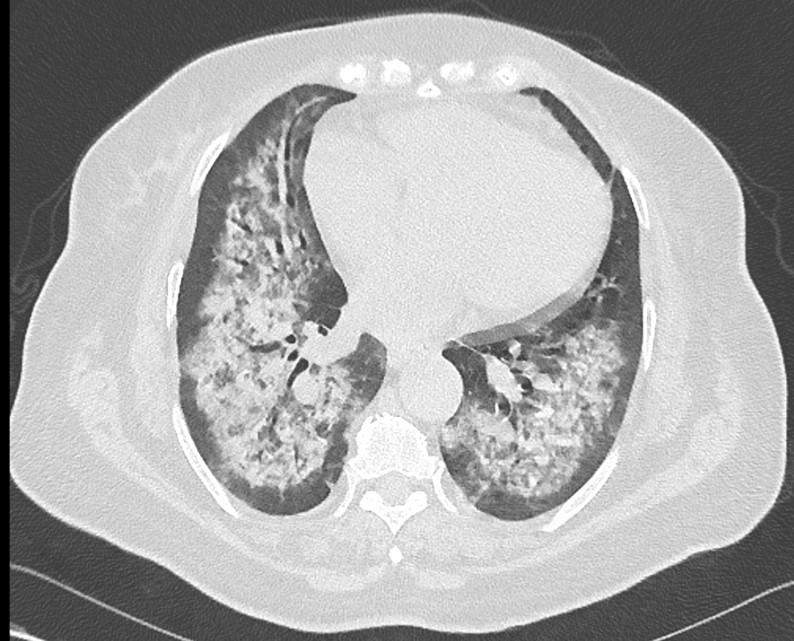

Vous confirmez la présence d’une protéinurie à 2,8 g/24 h. L’infirmière vous appelle car elle a constaté la présence de sang dans la sonde d’intubation. Un scanner thoracique est réalisé (figures 2a et 2b) :

Figure 2a (source : É. Crickx)

Figure 2b (source : É. Crickx)

Question 7 - Parmi les propositions suivantes, laquelle (ou lesquelles) est (sont) exacte(s) ?

Le scanner montre la présence d’opacités alvéolaires floues, confluentes et prédominant en périhilaire, tout en épargnant les régions sous-pleurales. Cet aspect est évocateur d’hémorragie intra-alvéolaire.